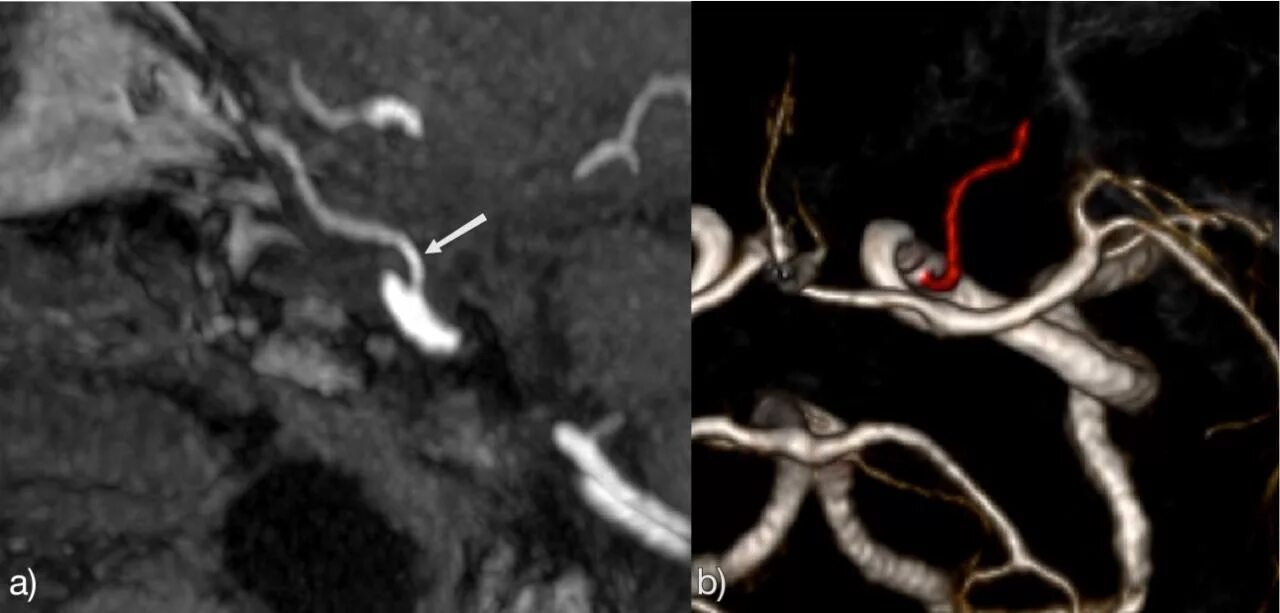

Гипоплазия сегмента v4 позвоночных артерий